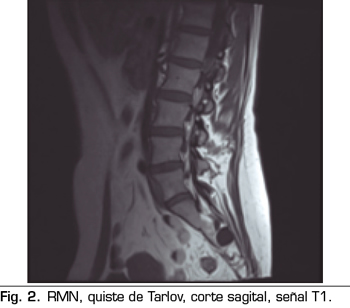

Se realiza una RMN donde no se observan alteraciones estructurales que justifiquen las dolencias que presenta. Como hallazgo casual se describen quistes de Tarlov a nivel de S2. Se solicita una valoración por el servicio de neurocirugía, quienes dudan que la clínica sea consecuencia de los quistes (Figuras 1 y 2).

No obstante, debemos tener en cuenta las variaciones anatómicas como son los quistes de Tarlov, a expensas de las capas más internas de las meninges, la piamadre y el aracnoides. Estos quistes principalmente se sitúan en la zona sacra y lumbar, y suelen diagnosticarse de manera incidental en el transcurso de una RMN. Aunque la clínica producida por los mismos no es frecuente, se deben tener en cuenta como posible diagnóstico diferencial ante posible dolor lumbar crónico.